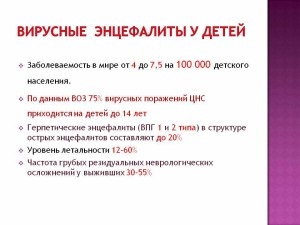

herpetică encefalita

Această formă principală de encefalita la copii este rar, dar cand apare, este nevoie de incredibil de dificil. Boala este al doilea tip de herpes virus, o sursă de distrugere este mucoasa nazală. In plus fata de simptomele encefalitic clasice la nou-nascuti dezvolta paralizie si herpes sepsis, care afecteaza ficatul si creierul.